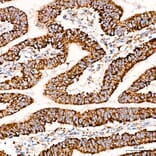

COX5A expression in human colon carcinoma tissue analyzed by immunohistochemistry. Tissue was paraffin-embedded, and antigen retrieval was achieved with 10 mM citrate buffer, pH 6.0, under high pressure. Staining was performed with Anti-COX5A Antibody (A329278) at a dilution of 1:100.